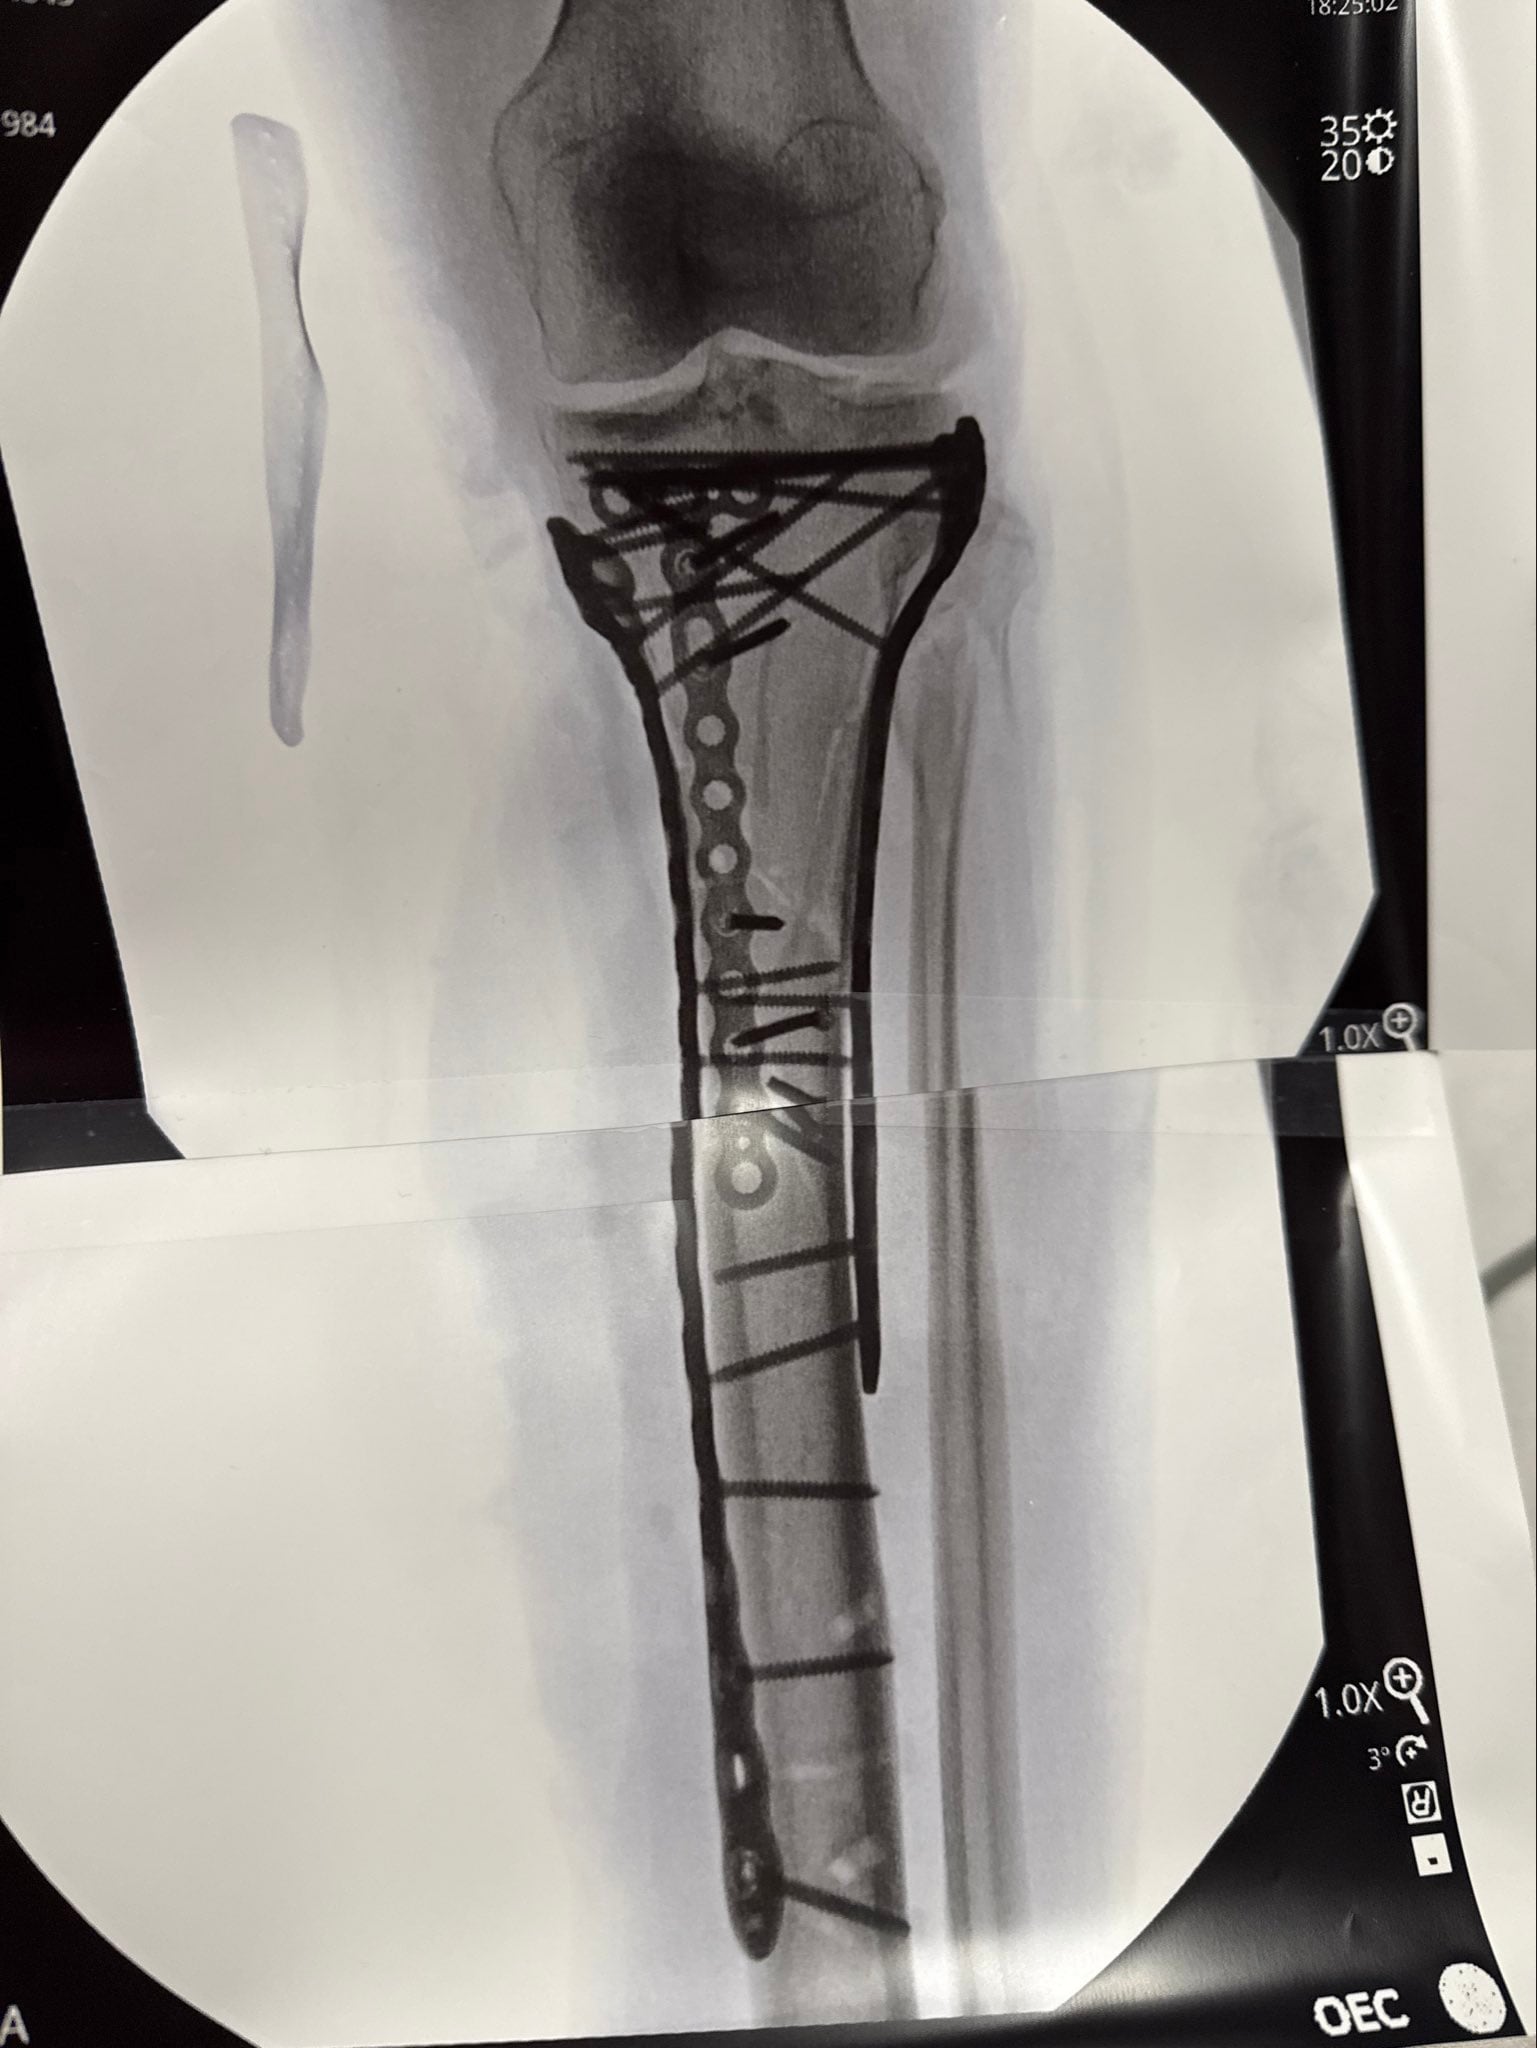

Ya en su perfil de Instagram, profundizó en sus sensaciones y lo acompañó de un video de ella en la camilla y una imagen de la radiografía en cuestión: “Como pueden ver han sido necesarias muchas placas y tornillos para recomponerlo todo. Debido a la gravedad del traumatismo, he tenido algunas dificultades después de la operación y aún no me han dado el alta del hospital… pero ya casi estoy lista. Pasito a pasito. Pronto explicaré la lesión y lo que significa todo esto”.

La mujer de 41 años fue sometida a cinco cirugías en menos de dos semanas, cuatro de ellas en Italia y una más en Estados Unidos tras lograr el alta médica y regresar a su país. La complejidad de la fractura en la tibia izquierda, combinada con el antecedente de múltiples lesiones previas y la existencia de implantes de titanio en su rodilla derecha, pone de relieve la magnitud de la situación. En palabras de la propia deportista: “Mi lesión fue mucho más severa que una simple fractura de pierna. Sigo asimilando lo que significa y el camino que tengo por delante”, escribió en redes sociales.

El doctor Bertrand Sonnery-Cottet, referente en ortopedia y cirugía de rodilla, advirtió en una entrevista con RMC Sports sobre el riesgo real que afrontan pacientes con lesiones tan graves: “Algunas lesiones como la suya pueden acabar en amputación”, aunque aclaró que el caso de Vonn no llegó a ese punto. El procedimiento más reciente, que duró más de seis horas, implicó la utilización de numerosas placas y tornillos para estabilizar la fractura. La atleta agradeció al equipo médico y relató que el dolor fue intenso, lo que dificulta su recuperación inmediata.